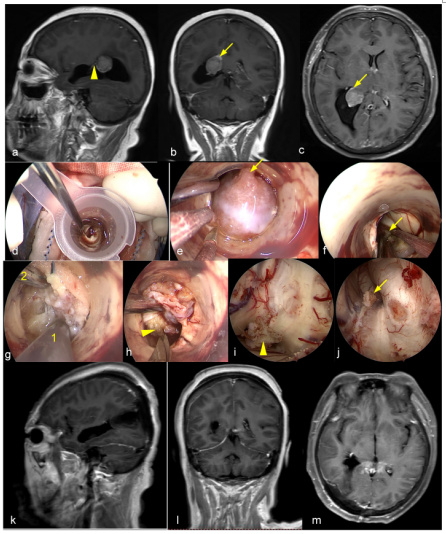

Neurosurgical Oncology Ward 3Neurosurgical Oncology Ward 3 (Middle-line skull base tumors and neuroendoscopy) Specialized features The Neurosurgical Oncology Ward 3 is characterized by the clinical application of neuroendoscopic technology. The annual number of neuroendoscopic surgeries exceeds 1200, and the quantity and quality of neuroendoscopic surgeries are leading domestically and internatio…